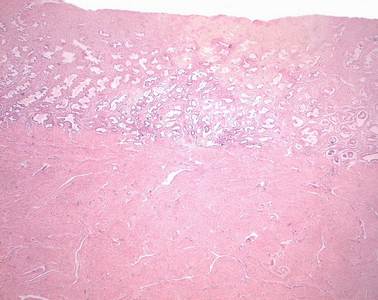

Präparat 82: Uterus, H.-E.

Wandausschnitt des Uterus. Im oberen Bildteil ist das Endometrium (Schleimhaut des Uterus) zu erkennen, das sich in ein an das Lumen grenzende Stratum functionale und ein darunter gelegenes Stratum basale gliedert. Im unteren Bildteil ist die kräftige Muskelschicht, das Myometrium zu sehen.

Endometrium

Tunica mucosa des Uterus, die dem Myometrium ohne scharfe Grenze folgt und zyklischen Verändungen unterliegt. Das Endometrium des Corpus uteri besteht aus einschichtigem hochprismatischem Epithel, tubulösen Drüsen (Glandulae uterinae) und einem als Stroma uteri bezeichneten Bindegewebe mit progesteron-empfindlichen interstitiellen Zellen. Es lassen sich das Stratum functionale und das Stratum basale, von dem die Schleimhautregeneration ausgeht, unterscheiden.

Stratum functionale

Funktionalis; dem Uteruslumen zugewandte, oberflächliche Schicht des Endometriums im Bereich des Corpus uteri, die starken Zyklusveränderungen unterliegt und während der Desquamationsphase abgestoßen wird. Ihre Regeneration erfolgt aus dem Stratum basale. Das Stratum functionale enthält senkrecht zur Oberfläche angeordnete, lange Drüsenschläuche, die Glandulae uterinae.

Stratum basale, Uterus

Basalis; dem Myometrium unmittelbar benachbarte, tiefe Schicht des Endometriums im Bereich des Corpus uteri, die während der Menstruation erhalten bleibt und die Grundlage für die Regeneration des Stratum functionale bildet.

Myometrium

besteht aus mehreren Schichten angeordneten glatter Muskulatur, die im Fundus- und Korpusbereich am stärksten ausgeprägt ist. Im Corpus uteri sind die innere und äußere Schicht hauptsächlich in longitudinaler Richtung angeordnet, während die aufgrund ihrer reichen Vaskularisation als Stratum vasculare bezeichnete Zwischenschicht zirkulär verläuft. Die zirkulär verlaufenden Faserzüge überwiegen im Bereich des Isthmus und der Cervix uteri.